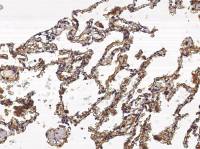

Bcl-2 antibody [GT11210] detects Bcl-2 protein at cytoplasm by immunohistochemical analysis.

Sample: Paraffin-embedded human tonsil.

Bcl-2 stained by Bcl-2 antibody [GT11210] (GTX628905) diluted at 1:50.

Antigen Retrieval: Citrate buffer, pH 6.0, 15 min